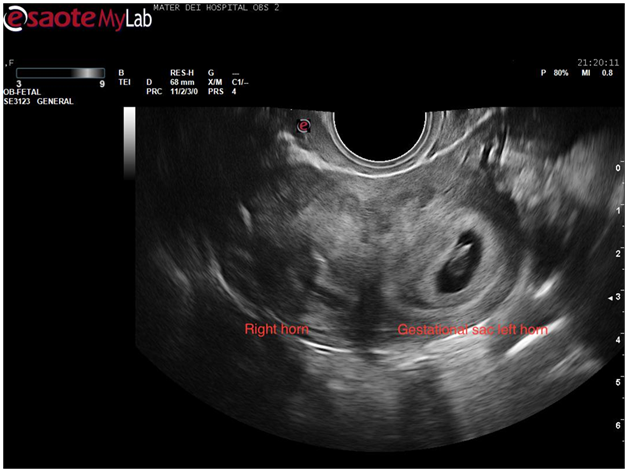

At this stage a decision was made to proceed to transvaginal scan in the hope of mapping the coils’ location better. Once again verbal consent was obtained and after covering the patient with a modesty sheet the high-frequency endovaginal probe was gently introduced after covering with gel and a probe cover. The images obtained confirmed the findings of the abdominal scan (Figure 5). By rotating the probe anticlockwise the uterus could be visualised in its transverse diameter. This view is a good one for demonstrating separation of the endometrial stripe into 2 as the uterus is scanned from a caudal to a cephalic direction. On reaching the fundus 2 definite horns are usually visualized (Figure 6). In this case, a gestation sac was distending the left horn as demonstrated in Figure 7. The rest of the examination was normal with both adnexae visualised and appearing normal.

Figure 7 Transvaginal scan showing a transverse view of the uterine fundus with 2 separate horns.